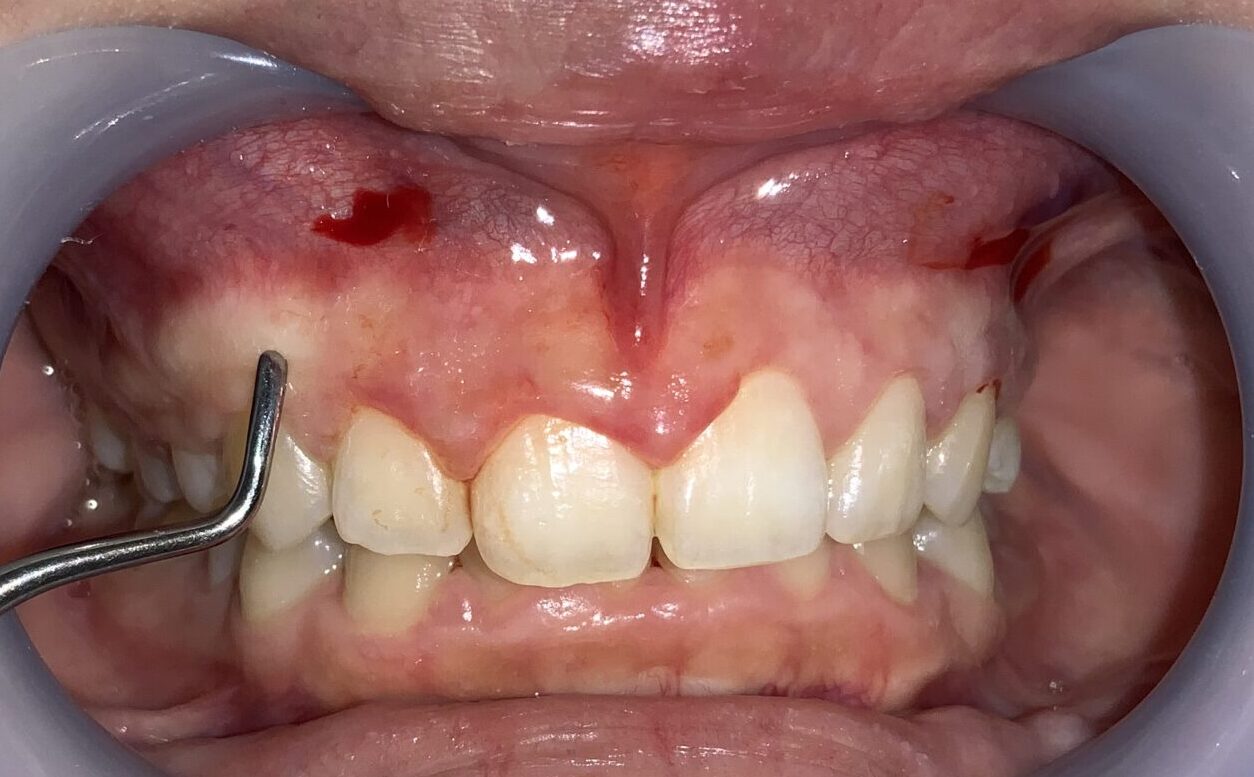

さらに隣の歯も検査します。

こちらの歯は犬歯です。大きく切り取り過ると、八重歯になってしまうので、注意が必要です。

安全に切除できる範囲の歯ぐきを計測します。

反対側の歯の検査に移動します。

血液が出ているのは、局部麻酔の影響です。歯の検査の影響ではありませんので、ご心配なく、検査をお受けください。

歯ぐきの厚みや歯槽骨の状態も確認します。

この歯も歯ぐきが被っている量が相当あります。